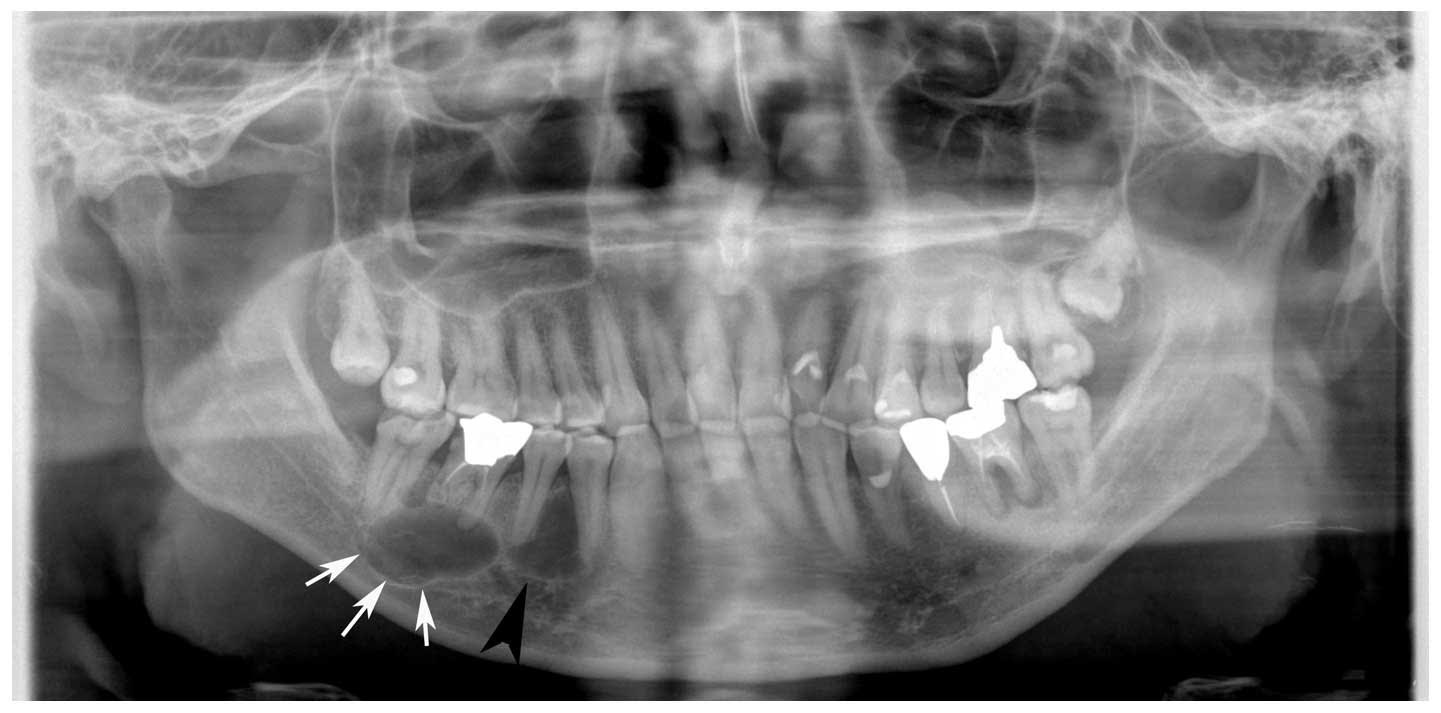

Çene kistleri ağrıya sebep olmadan yavaş büyüdükleri için kolayca tespit edilemezler. Rutin alınan bir radyografide tesadüfen görülebilirler. Bazen de çok büyüdükleri zaman sinire baskı sonucu uyuşukluk, çene kırıkları, komşu dişlerin yer değiştirmesi gibi belirtilerle kendilerini gösterebilirler.

-Çene sinirine yakın bölgedeki kistler büyüyerek sinire baskı yapar ve uyuşukluğa sebep olabilirler.

-Komşu dişleri iterek yer değişikliklerine ve sallanmalarına sebep olabilirler.

-Çok büyük boyutlara ulaşınca çene kırıklarına sebep olabilirler.